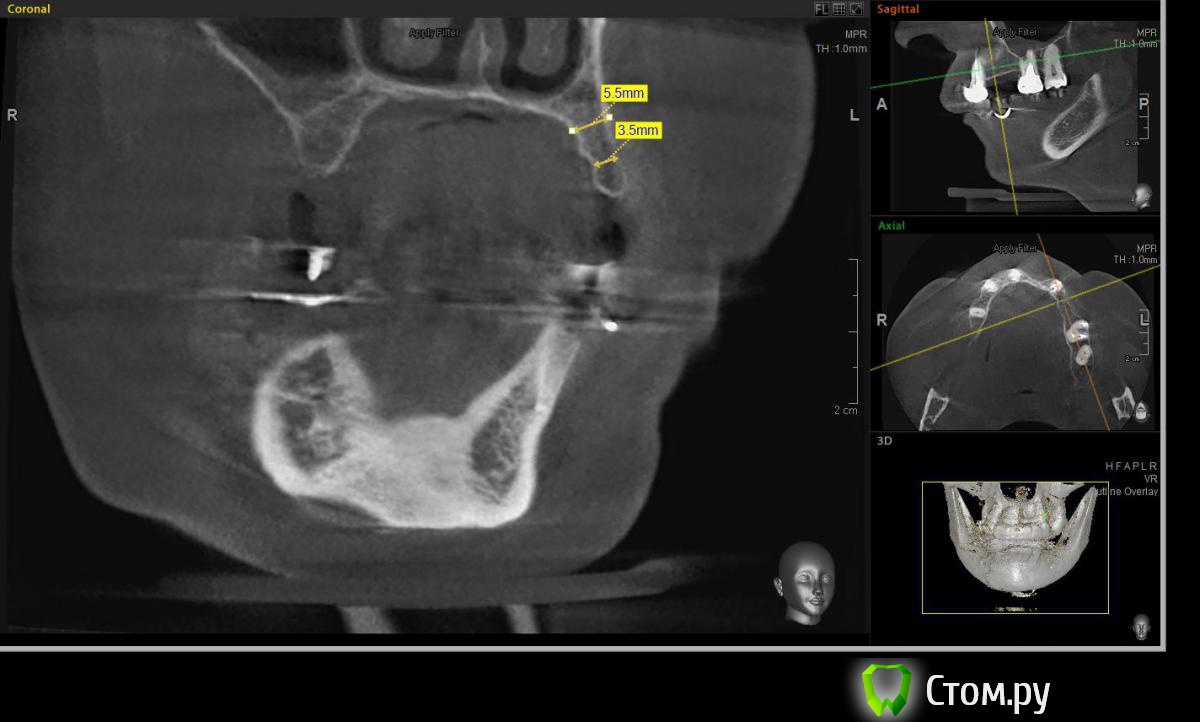

Евгений Ходыкин Опубликовано 22 июля, 2014 Автор Поделиться Опубликовано 22 июля, 2014 Дабы не плодить тем решил очередной случай выложить сюда Решили с пациенткой пока начать с в.ч. В планах имплантация в область отсутствующих 1.6, 1.4, 1.2, 2.1, 2.2, 2.4, 2.5. С 1.6 самому более менее все понятно, мануальных навыков хватит) Прошу помощи коллег относительно остальных областей. Фронт особливо печален... Забегая наперед скажу, что блоки еще не делал. Ауто точно пока брать не планирую, ибо нет даже теоретических навыков. Хочу начать все-таки с аллоблоков. У кого какие будут мнения, заранее спасибо) Ссылка на комментарий